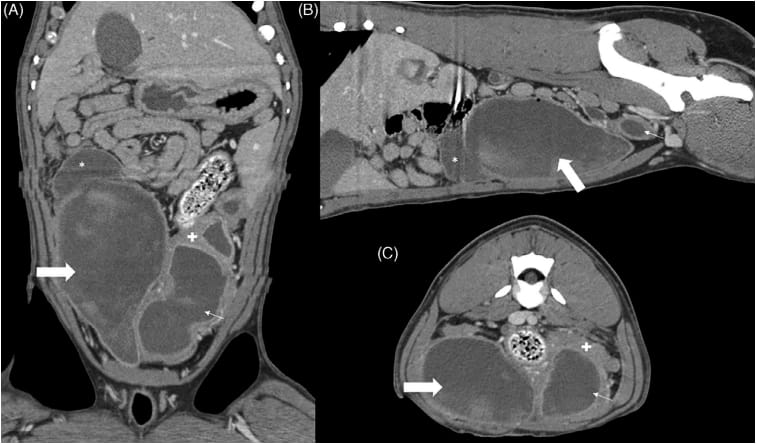

Dorsal (A), sagittal (B), and transverse (C) CT images postcontrast medium administration centered at the level of the urinary bladder

and uterus. At the apex of the bladder is a crescent-shaped-fluid-filled cavity (*), increased in size from the ultrasound examination (Figure 1) which

communicates with the urinary bladder. The bladder (thick arrow) contains some relatively hyperattenuating material, similar in character to the left

uterine horn (thin arrow). The uterine wall is moderately thick (+).